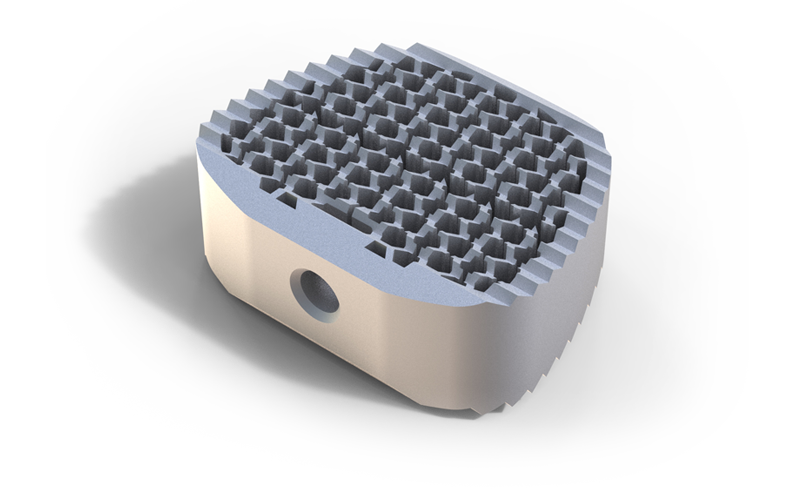

Cages

Alle Modelle nun mit der patentierten hygroskopischen Struktur. Diese Kapillarwirkung beeinflusst das Einwachsverhalten positiv ohne Verwendung von autologem Knochen.

HYGROCervicaler Cage aus Titan

Hygro ist ein Unikat auf dem Markt. Wie der Name schon sagt werden durch eine spezielle Anordnung der Lamellen im Inneren des Cages optimale hygroskopische Eigenschaften erziehlt. Eine Fusion wird hierbei erzielt ohne den Cage mit autologem Knochen oder Knochenersatzmaterial zu befüllen.